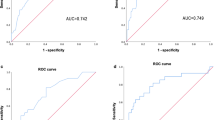

The AUROC of the model was 0.920 (95% CI 0.902–0.938), indicating a greater capability to discriminate NCP than WBC count (AUROC 0.727, 95% CI 0.692–0.762) or chest imaging score (AUROC 0.795, 95% CI 0.766–0.825) (Fig. 1). To internally examine whether the model was over fitted, we used fivefold Cross-Validation of the trained model, and repeated the cross-validation for 10 times. It showed that the mean of AUROC was of 0.916 with the standard deviation of 0.017. The Hosmer–Lemeshow test which measured the calibration showed a χ2 of 10.857 (P = 0.210), demonstrating that there was no significant difference from a perfect fit. The patients with NCP had a model score of 3.60 ± 2.41, higher than those without NCP (model score = −0.42 ± 1.69, P < 0.001) (Fig. 2). At a cut-off value of 1.0, the rapid screening model could determine NCP with a sensitivity of 85% (95% CI 81.2–88.8%), a specificity of 82.3% (95% CI 80.6–84.0%), a diagnostic accuracy of 83.2% (95% CI 80.7–85.7%), and a Youden index of 0.673.

The capability of the models to discriminate novel coronavirus pneumonia. The three panels illustrate the performance of three models trained in this study. In each column the figure atop plots the fitted distribution of the predicted scores for the cases (blue) and the controls (green), respectively. The small vertical ticks underneath the distribution curve are the detailed predicted scores for individual, and the estimated mean scores of the model are presented in colored vertical lines. In the bottom plot the receiver-operating characteristic (ROC) curves (red) with the point-wise 95% confidence intervals (grey) for the corresponding prediction model. The area under the ROC curve of model 1 (the primary predictive model), model 2 (the simplified model), and model 3 (model without epidemiological history) was 0.920 (95% CI 0.902–0.938), 0.909 (95% CI 0.889–0.929), 0.859 (95% CI 0.833–0.884), with a standard error of 0.009, 0.010, and 0.013, respectively.

Simplified model score (model 2) = 1 (if contacting patients with fever or respiratory symptoms from areas with persistent local transmission or community with definite cases within 14 days) + 3 (if relating to a cluster outbreak) + 1 (if having fatigue) + 2 (if having dyspnea) – 1 (if having nasal congestion) + 3 (if feeling muscle soreness) − 0.3 * WBC count + 2 * pulmonary imaging score. The AUROC was 0.909 (95% CI 0.889 – 0.929) (Fig. 2). In fivefold Cross-Validation, the average AUROC was 0.862, with the standard deviation of 0.028. The Hosmer–Lemeshow χ2 was 11.962 (P = 0.153). The optimal cutoff value was 0.7, with a sensitivity of 82.3% (95% CI 76.3–87.0%), a specificity of 86.2% (95% CI 82.9–88.9%), a diagnostic accuracy of 84.6% (95% CI 82.2–87.0%), and a Youden index of 0.685.

Model score without epidemiological history (model 3) = 0.6 (if having coexisting diseases) + 0.8 (if having fatigue) + 1.2 (if having dyspnea) + 2.4 (if feeling muscle soreness) − 0.3 * WBC count − 0.3 * Lymphocyte count + 1.6 * pulmonary imaging score. The AUROC was 0.859 (95% CI 0.833–0.884) (Fig. 2), with the optimal cutoff value of − 1, a sensitivity of 83.5% (95% CI 79.1–87.1%), a specificity of 76.0% (95% CI 72.1–79.4%), a diagnostic accuracy of 78.9% (95% CI 76.2–81.7%), and a Youden index of 0.595. Repeated fivefold Cross-Validation showed the average AUROC was 0.854, with the standard deviation of 0.027. The Hosmer–Lemeshow χ2 was 12.218 (P = 0.142), indicating no statistical difference from a perfect fit.